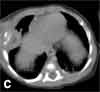

A chest CT scan with contrast showed a chest wall mass of 1.3 3 1.8 3 2 cm displacing the lateral segment of the right middle lobe, contiguous with a bilobulated intra-extrathoracic mass with necrotic centers and thickened irregular walls of 2 cm (C).

The mass involved the distal end of the right seventh rib, which had an irregular bony cortex.